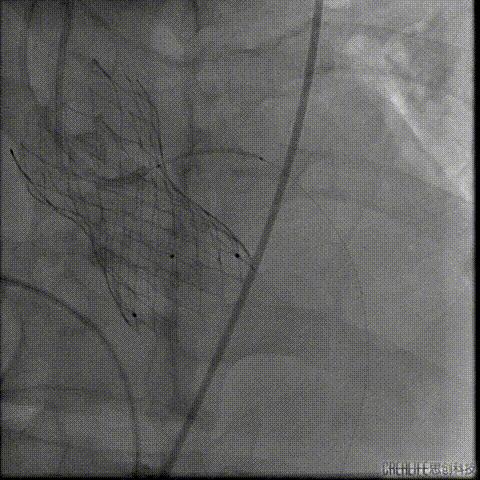

置入4.0mm*23mm微创冠脉支架

定位并释放支架

退出球囊扩张突入瓣架部位

复查冠脉造影

多体位复查冠脉造影